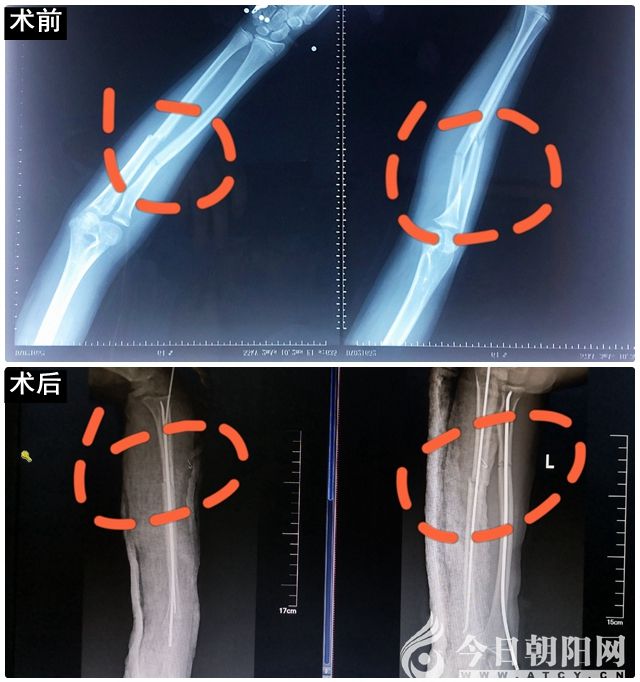

患兒女性,9歲,因車(chē)禍?zhǔn)軅伦笄氨鄢邩锕枪钦郏钦蹫椴环€(wěn)定骨折,移位明顯,非手術(shù)不能滿(mǎn)意復(fù)位。為了使手術(shù)給孩子造成的副損傷降到最低,創(chuàng)傷骨科副主任、主任醫(yī)師李榮華帶領(lǐng)副主任醫(yī)師唐磊、主治醫(yī)師王海軍在術(shù)中C臂X光機(jī)透視下為患兒實(shí)施了骨折閉合復(fù)位彈性髓內(nèi)針固定手術(shù),手術(shù)過(guò)程順利。參與手術(shù)的醫(yī)生術(shù)后無(wú)私地說(shuō):“為了孩子得到最好的治療,多受一些X線(xiàn)輻射也值了。”